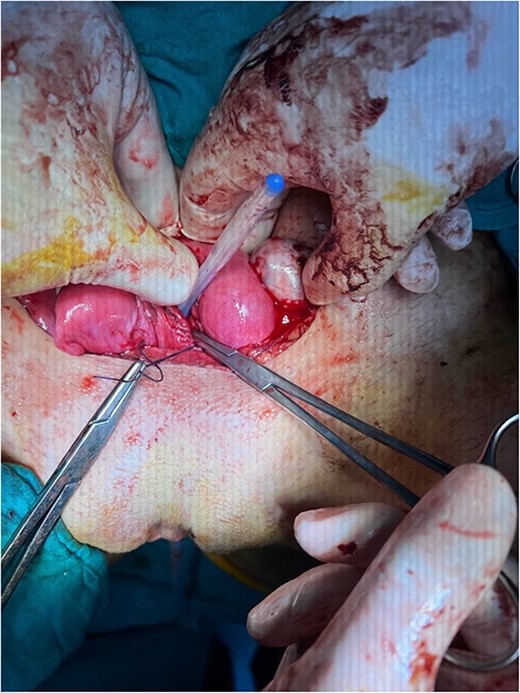

By surgically opening and reaching the abdominal cavity, two uteruses were found, along with a mass filling the pelvic cavity, measuring about (8 × 7 cm). We also saw a didelphys uterus with normal right and left ovaries, a hematoma filling the left fallopian tube, and an accumulation of blood within the vagina (hematocolpos) (Fig. 3).

(A) A hematoma in the left fallopian tube. (B) An accumulation of blood in the vagina.